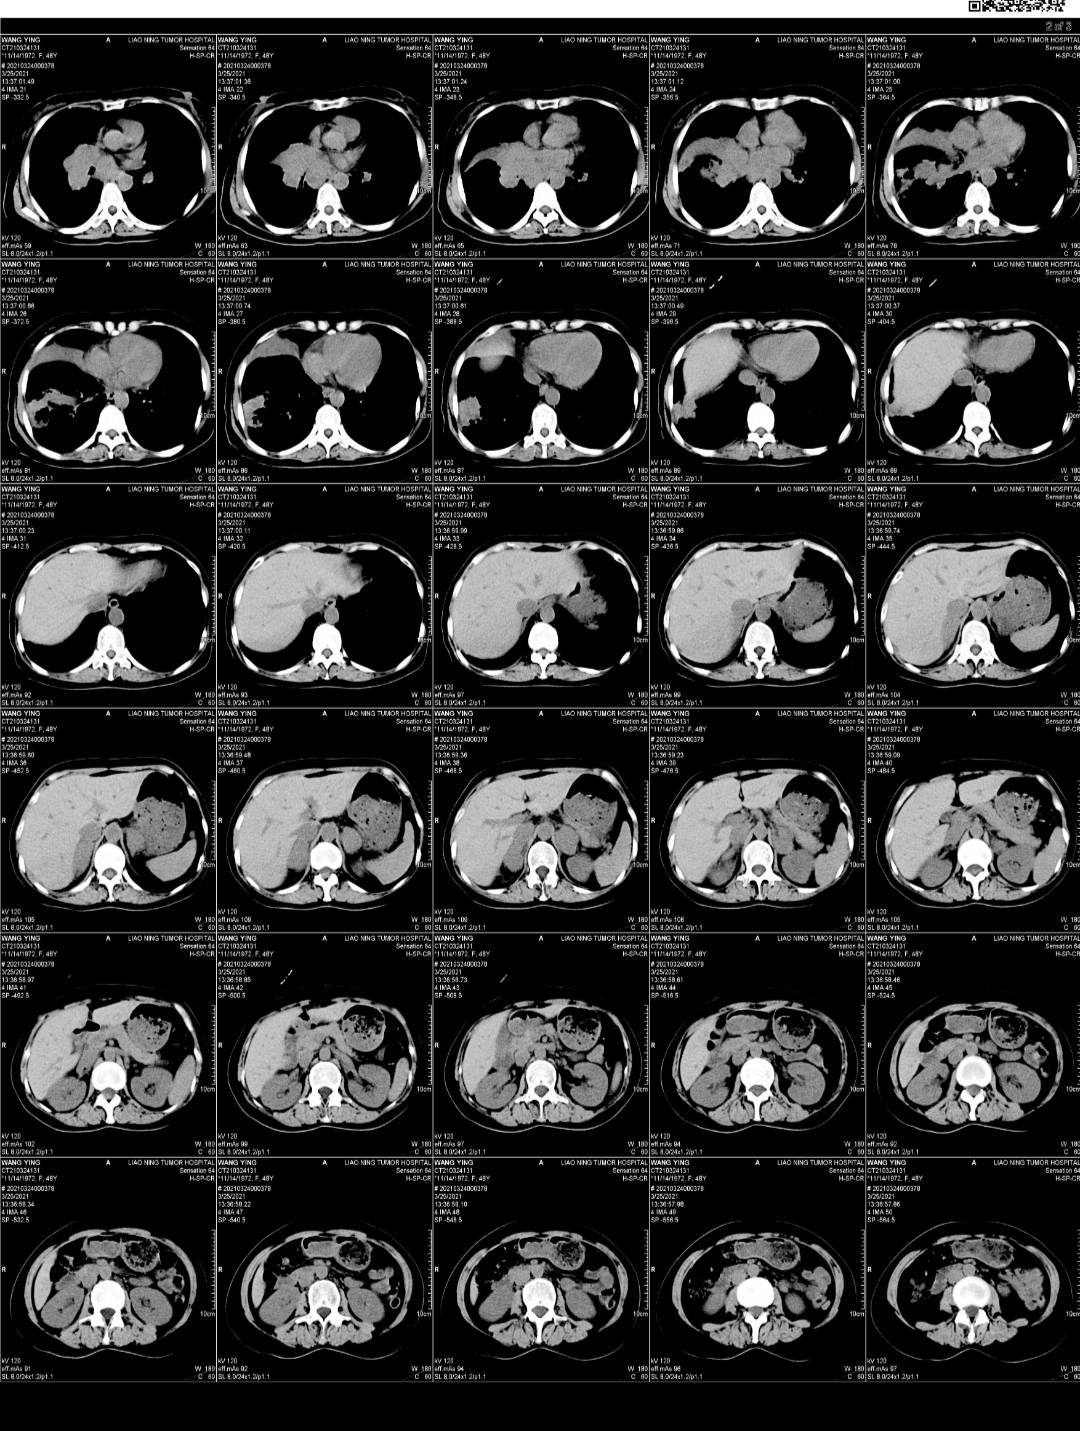

3.24吃一个月凯美纳 复查,打唑来膦酸第二针,当天看到血的结果就觉得不对劲,一些指标还在升高,就跟医生联系,她也觉得不对劲,说等ct再看看。

25号下午做的ct,当天晚上我就在手机上看到了报告,没写大小,感觉不妙,心里非常慌。

今天早上让爸爸取完ct就发给我,真的是没有好转。

下周一穿刺取病理,看看有可能是小细胞吗?